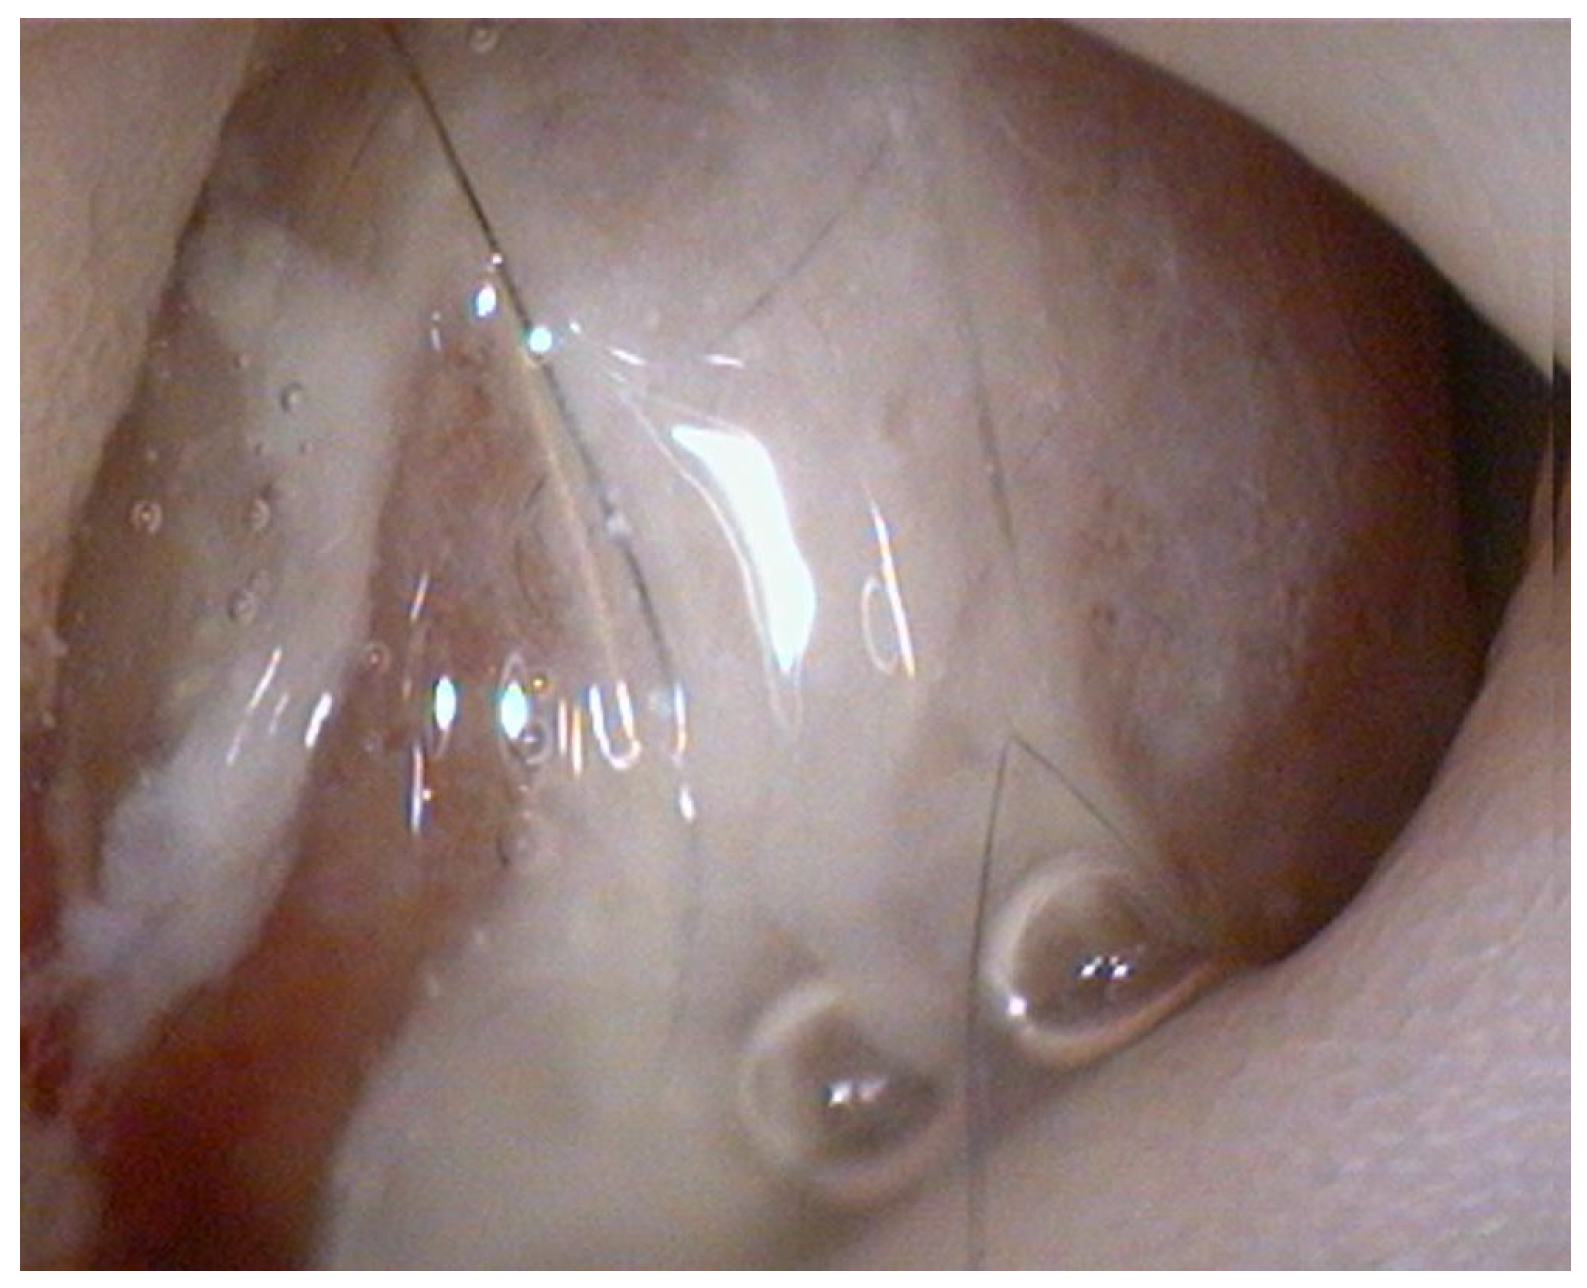

The endoscopy demonstrated complete resolution of the duodenal mass, which was replaced by a well- demarcated focal mucosal depression at the site of the previous lesion (Figure 3).

Figure 3. Endoscopic view showing mucosal depression.